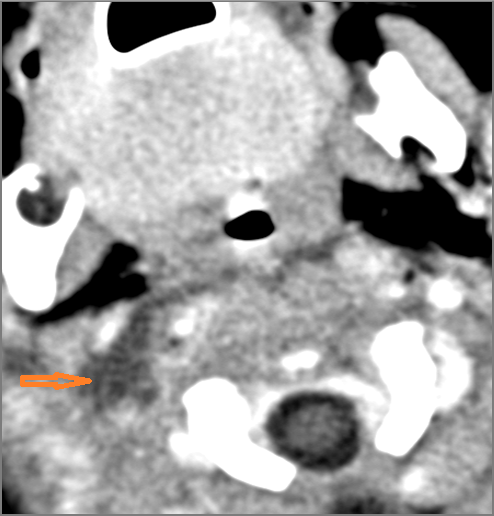

Cervical Lymph Nodes

There is reactive cervical lymphadenopathy. [Yes/No]

There is suppurative cervical lymphadenopathy. [Yes/No]

If there is suppurative cervical adenopathy the purulent material outside the lymph node(s) capsule(s). [Yes/No]